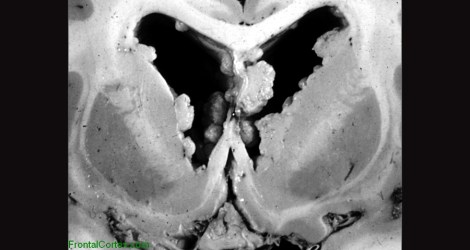

The well-known autism-associated condition, Tuberous Sclerosis, is also typified by heterotopias, specifically within the periventricular area. Rather than exhibiting focalized heterotopias, people with TSC often have multiple nodular heterotopias, as shown in the image below. Most cases of TSC are due to mutations in the TSC1 and TSC2 genes which are negative regulators of the growth-related Akt pathway. As you can imagine, if one of these genes are knocked out, then activity of Akt increases and subsequently increased cellular growth and proliferation ensues.

Image of periventricular heterotopias, borrowed from here.